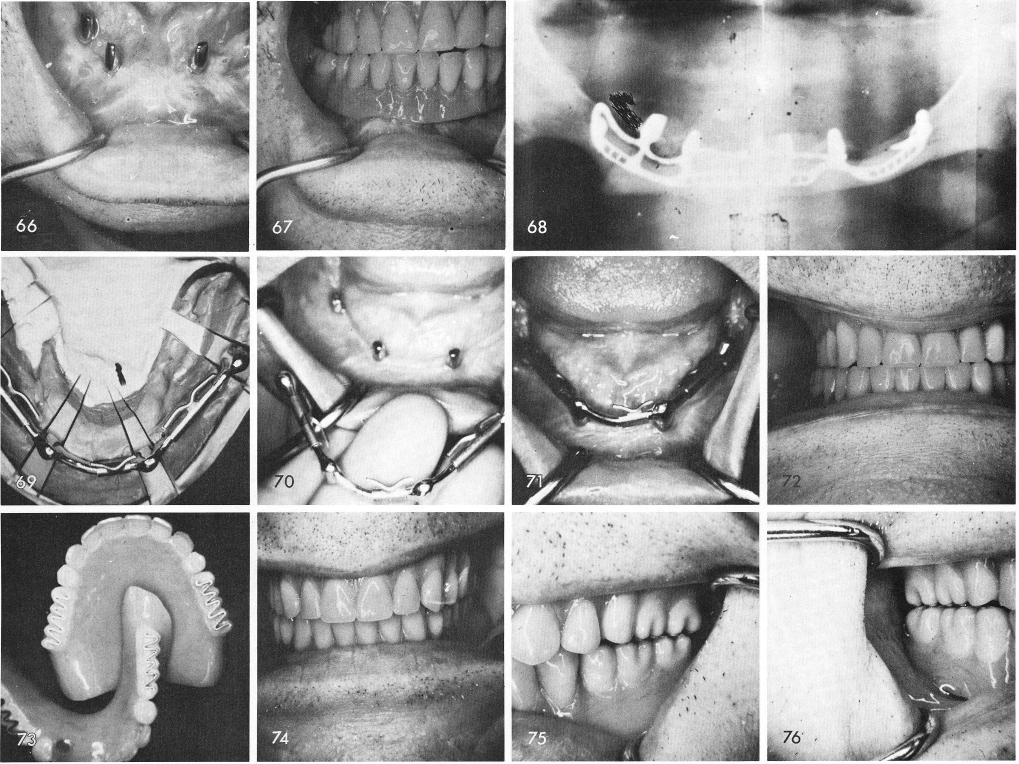

expectations, fig. 66, and the implant denture was fitted to place, fig. 67. Although asymmetry of both sides of the jaw existed, the patient wore this appliance successfully for more than six years before he had a heart attack and died. The post-operative x-ray, fig. 68.

Many problems occurred with the retention of the dentures after several years with the early designed extremely short posts. Internal clasps broke reducing the overall retention of the implant denture even though the implants were successfully functioning.

Before I started designing the posts to be much larger, improvising the existing short posted subperiosteal implants had to be done. Dolder or Andrew type bars attached to gold copings were used with internal clips, figs. 69, 70, 71, 72. Sometimes Hardy posterior teeth are used in those cases where patients require a sharper grinding apparatus, figs. 73, 74, 75, 76.

1 Dolder type bars attached to gold copings over mandibular implants